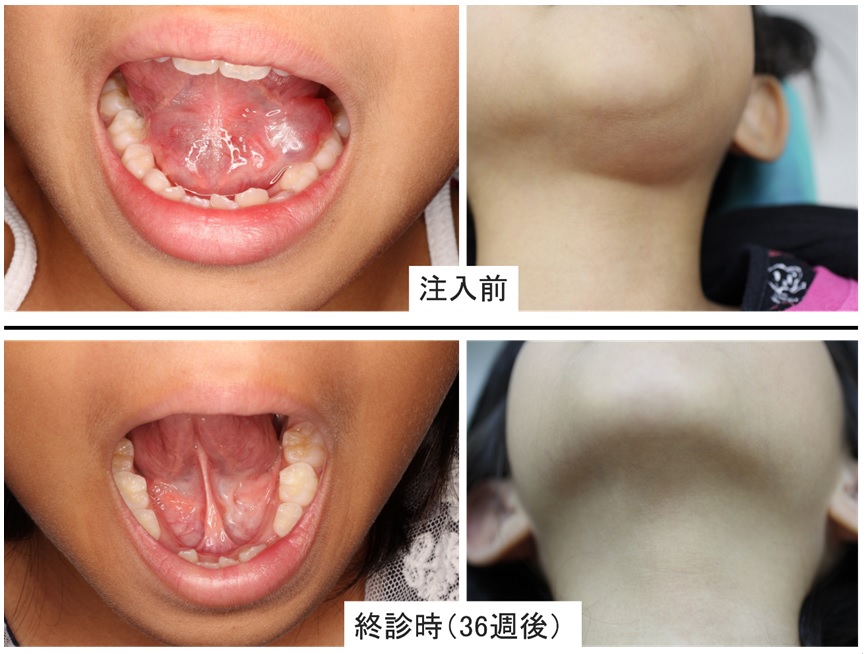

ガマ腫・・・OK-432嚢胞内注入療法

ガマ腫とは舌下腺から分泌される唾液が周囲にたまり、腫瘤の様に腫れる嚢胞性疾患です。 見た目が、ガマ蛙ののど袋に似ているのでガマ腫と命名されています。ラヌーラとも呼ばれます。

当院ではOK-432(ピシバニール)という抗悪性腫瘍剤を嚢胞内に注入する保存療法を行っております。OK-432を注入する事で嚢胞内に炎症が起こり舌下腺から唾液が漏れている部位に作用して治癒します。

副作用としては発熱と腫脹があります。またOK-432はA群溶連菌Su株をペニシリンで不活化した製剤であるためペニシリンアレルギーがある方は使用出来ません。

一度で効果が出ない場合は繰り返し行います。それでも治癒しない場合は舌下腺摘出の外科的な手術療法を行います。